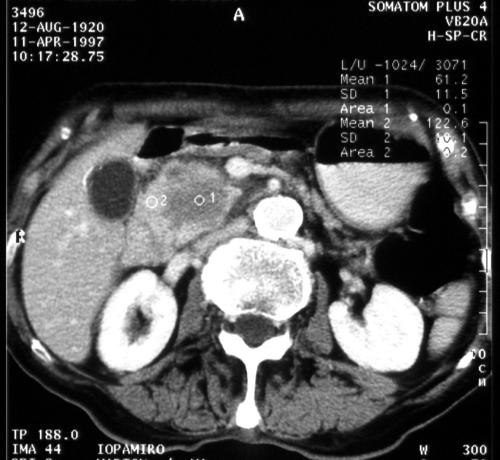

Figure 2. A 52 year old male with icterus. Spiral CT after contrast medium administration shows a hypodense 3 cm diametered lesion in the processus uncinatus. Ductal adenocarcinoma

A circumscribed mass is the primary, but not necessarily an early sign of ductal pancreatic adenocarcinoma. An increase in diameter and roughness of the contour of the pancreas are unreliable signs of malignancy. The masses contained a central zone of diminished attenuation in about 80% of the cases [4]. On unenhanced CT most tumors have the same density as normal pancreatic tissue and can easily be missed if the tumor is small and the contour of the gland is not deformed. With spiral CT and bolus contrast administration, the tumor-pancreas contrast is best seen during the early phase of pancreatic perfusion. The tumor as a hypodense lesion can be distinguished from the opacified pancreatic parenchyma. A cystic central portion can demonstrate necrosis or the hemorrhage in the tumor. The border between the pancreas and the retroperitoneal space and the surrounding organs is often indistinct [5].

Reaction surrounding the tumor occasionally creates a fuzzy appearance of the tumor region mimicking pancreatitis. The high contrast of peripancreatic vessels on contrast-enhanced CT allows assessment of vascular encasement. Staging of pancreatic carcinoma with conventional CT involves only the major peripancreatic arteries and veins. Helical CT can sufficiently show enough small arteries (gastroduodenal artery, anterior and posterior superior pancreaticoduodenal arteries and the right gastroepiploic artery) to allow evaluation in the preoperative staging of pancreatic tumors [8]. CT findings of dilatation or obstruction of the superior peripancreatic veins (pancreaticoduodenal veins and gastrocolic trunk) suggest tumor extension to the peripancreatic tissues. The small veins are difficult to detect on conventional CT, but helical CT enables a more precise identification of the inferior peripancreatic veins [9, 10, 11].